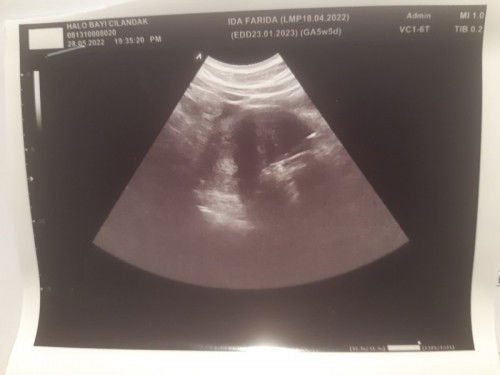

USG 5w tapi blm paham sama hasilnya semoga aj jadi baby

USG 5w hasilnya kaya gini disuruh usg lg 2 minggu kemudian..kira2 ada ngerti g maksud dr hasil itu krn kmrn wktnya g lama sebab dokternya ada pasien tindakan yg harus segera ditangani jd g bs nanya banyak#seriusnanya #ingintahu

5 week paling baru penebalan dinding rahim bun, itu juga hasil usg nya blm ada keteranga apa² nya krn emang masih penebalan. dikasih vitamin dan asam folat? diminum yaa. ikuti intruksi dokter untuk balik 2 minggu lagi , semoga berkembang jadi kantung janin yaa.. sehat selalu.